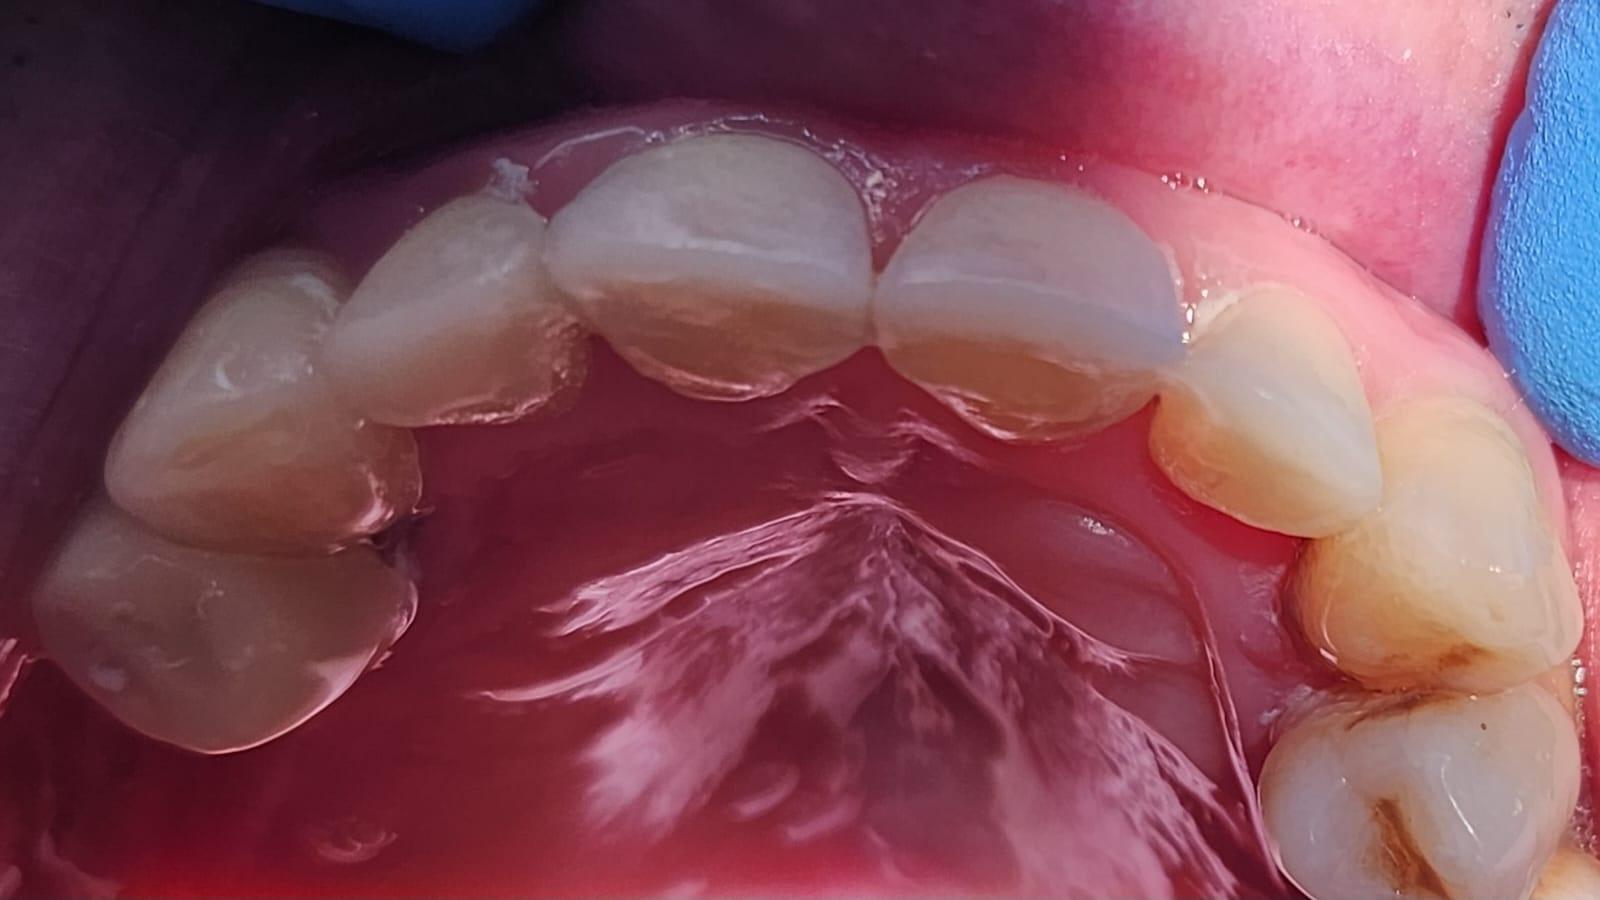

Clinica LUY ESTHETIC ART defineste parodontoza ca fiind rezultatul direct al placii dentare, care se depune pe suprafata dintilor, dar si in apropiere de marginea gingivala. Aceasta boala duce la pierderea dintilor, chiar daca ei sunt aparent sanatosi si nu prezinta carii. Edentatiile, afecteaza vorbirea, aspectul, dar si capacitatea de a mesteca.

Boala parodontala are un caracter progresiv. Pentru cazurile mai grave, recomandam tratamentul parodontal chirurgical rezectiv sau regenerativ.

– retractii gingivale cu expunerea radacinilor dentare;